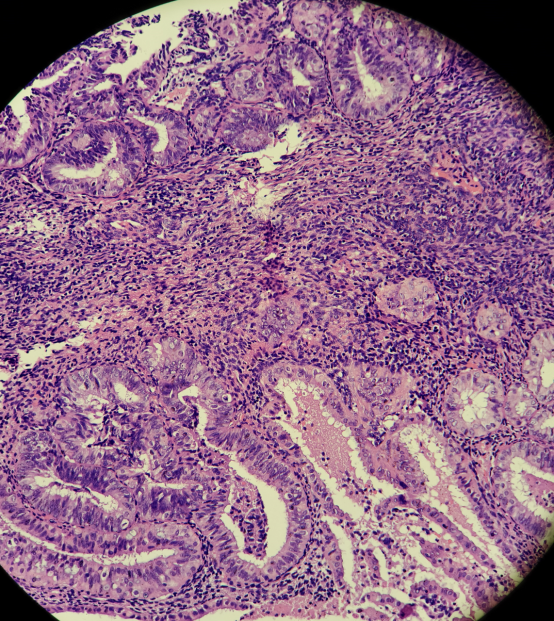

HE染色切片:

结果判读:组织中可见多灶性病变区域同时出现PTEN和PAX2的表达缺失。结合形态学改变,支持AH/EIN的诊断。